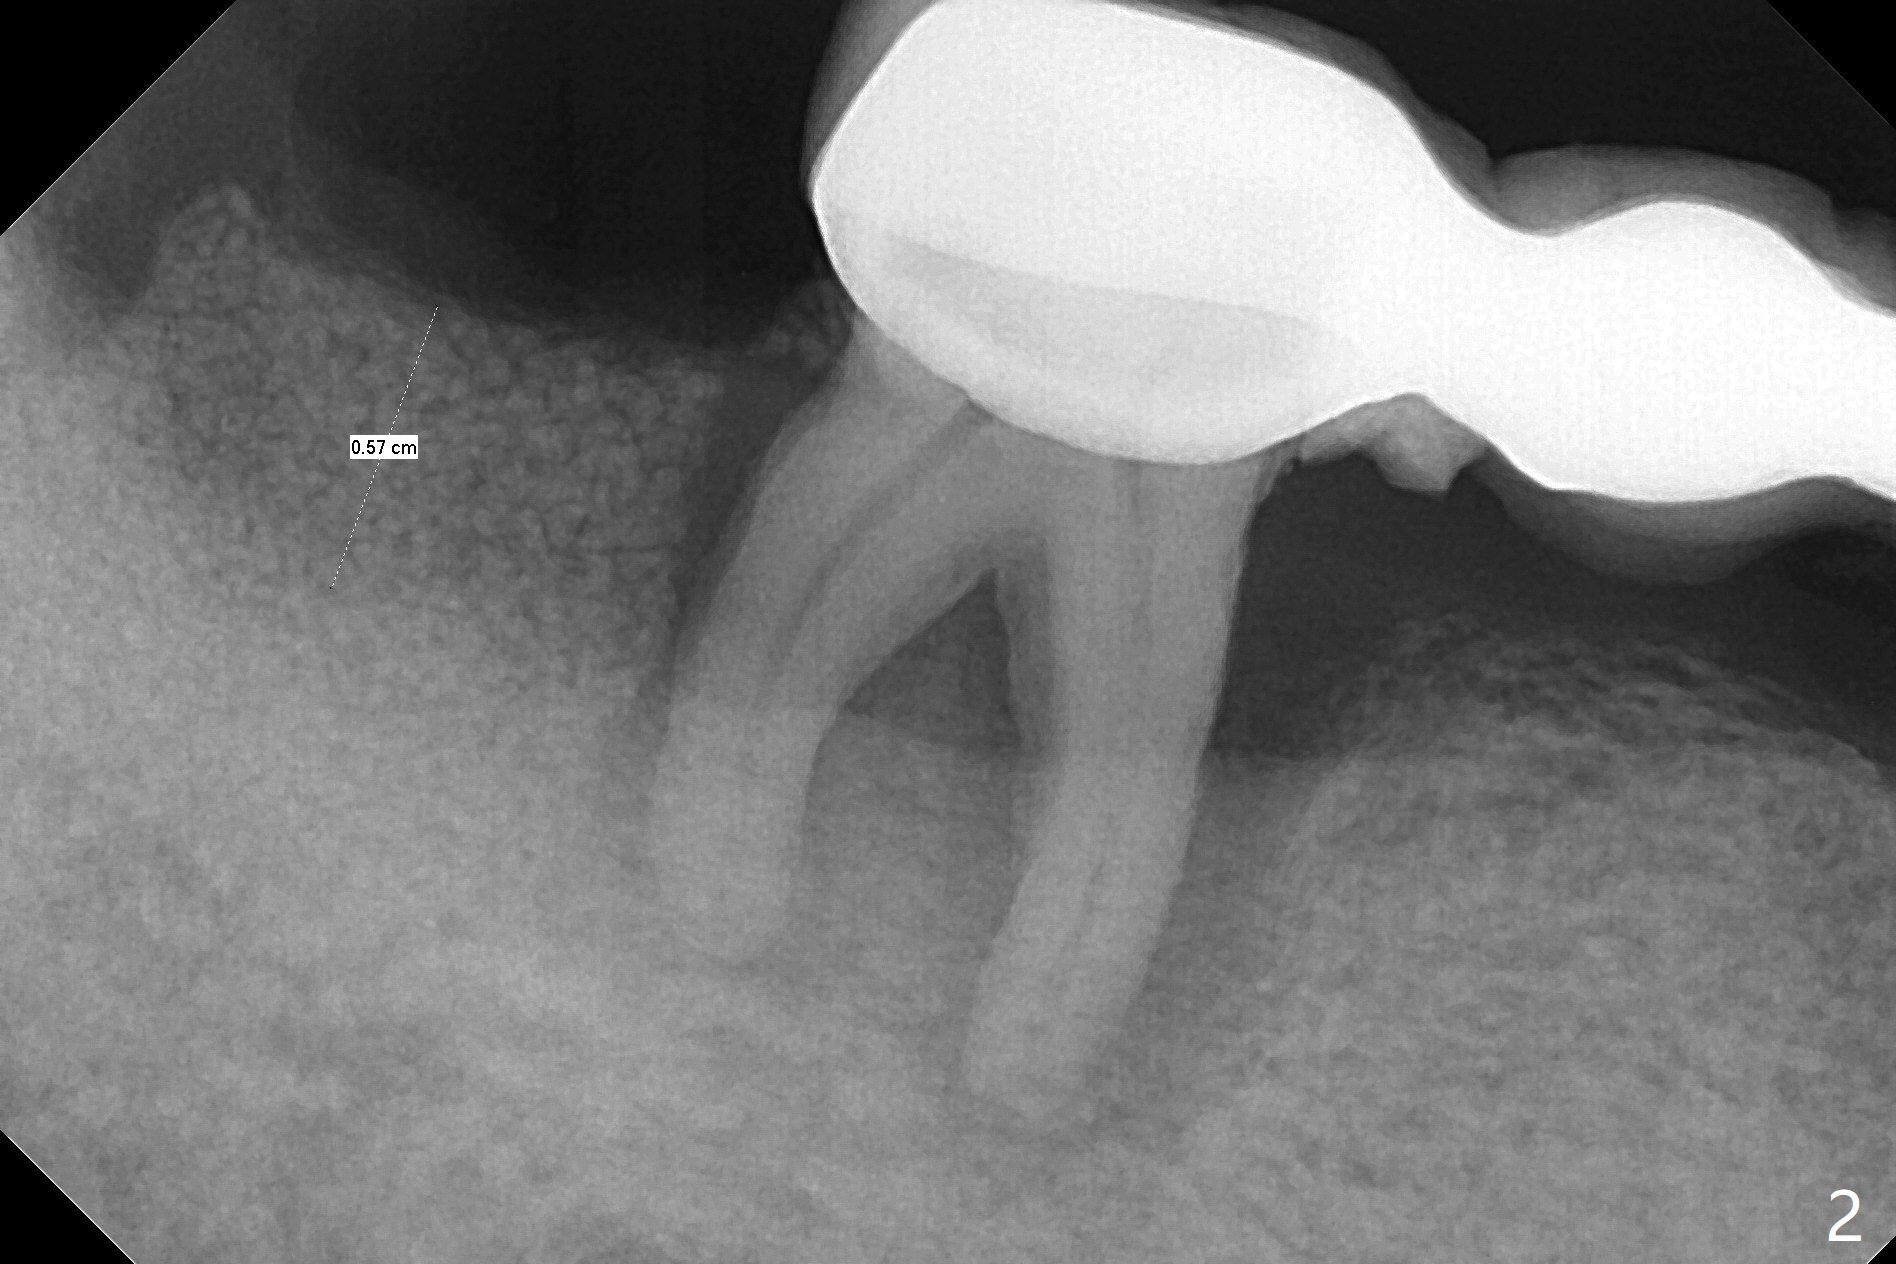

44岁男,吸烟,一天半包,严重牙周病,左上托牙,右下7骨质吸收(图一),松动,影响吃饭,起初他不同意植骨,后来改变主意。拔牙时发现牙龈袋特别深,清创(包括近中)后,放置许多骨粉(皮质),骨高度至少增加5-6毫米(图二)。不可吸收膜,PTFE缝线。如果以后6号牙需要拔除(图三黑色),为了维持龈乳头,牙间牙龈下部分应该切除(图四橘黄色),空间由骨粉充填(图五红色圆圈),以便重新建立牙间牙槽嵴。